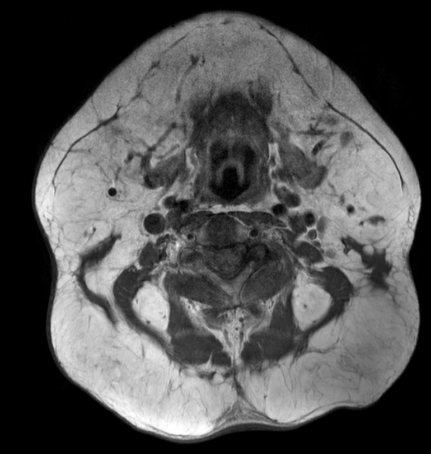

本例患者是一位66岁的男性,近在两年多的时间里出现了颈枕部大量的软组织生长(图1)。他酗酒严重,但没有相关病史。体格检查显示前颈部(马德龙项圈)弥漫性增大,后颈部有三个巨大隆起。内分泌检查结果正常,实验室检查(包括血脂)未发现异常。术前进行磁共振成像(MRI)以区别于其他疾病,如病态肥胖症、神经纤维瘤病、库欣综合征和淋巴瘤(图2),结果显示颞部和枕部以及颈部I-III和V级和后颈部的对称性大量脂肪增生,这与MD的诊断一致。

图2